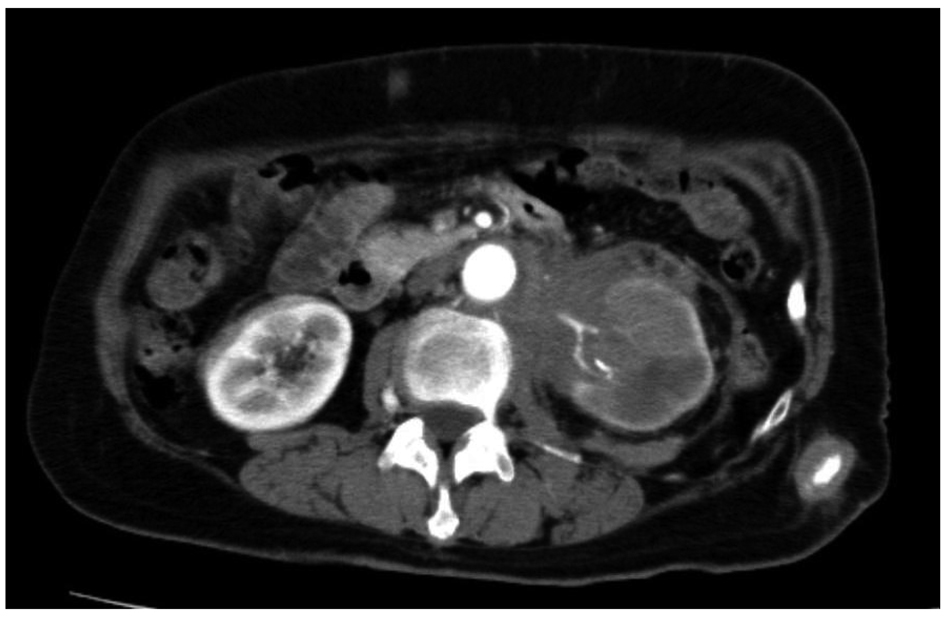

A 73-year-old female patient presented with left back pain and subcutaneous abdominal nodules. The lesions were tender, firm, and fixed. A computed tomography scan showed a mass around the left renal hilum and subcutaneous abdominal masses (Fig. 1). She was referred to our hospital. Retrograde pyelography showed an obstruction in the upper urinary tract. Urinary cytology of the ureter was negative. Magnetic resonance imaging, gastrointestinal endoscopy, and colorectal endoscopy showed no other abnormalities. Biopsy of a subcutaneous mass was performed. The mass was 1.5 cm in diameter, yellowish-white, solid, and encapsulated (Fig. 2a). Pathological findings showed proliferation of atypical cells infiltrating the subcutaneous fat tissue in nests and cords throughout the dermis with no involvement of the overlying epidermis. These atypical cells were positive for CK7 and CK20 (Fig. 2b, c, d). She was diagnosed with TCC of the left renal pelvis with metastasis to the skin (cT4N0M1).

![]() Click for large image | Figure 1. Computed tomography showed a mass around the left renal hilum and subcutaneous abdominal masses. |